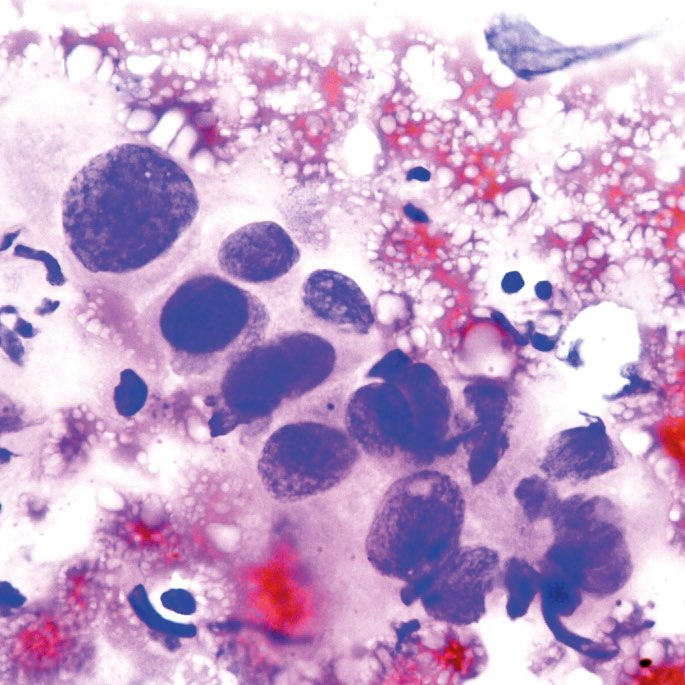

Abb. 1 - 4: Ausstrich von Milchröpfchen; H&E, A-C: origin. Obj. 40x,

Abb. 4: zusätzlich etwas vergrößert

Beschreibung

Viele Makrophagen, darunter auch eine mehrkernige, mit fein-granulärem bis fein-vakuolärem Zytoplasma (Abb. 1-4). In Abb. 4 eine Gruppe von Epithelien mit uneinheitlich geformten hyperchromatischen Kernen und mehr grob-vakuolärem Zytoplasma. Der Ausstrichhintergrund enthält massenhaft bläschenartige Lipidtröpfchen.

Kommentar

Als Galaktorrhoe bezeichnet man Milchfluss außerhalb der Schwangerschaft und Stillperiode. Ursache ist eine erhöhte Prolaktinbildung in der Hypophyse. Sie kann durch einen Tumor von Hypophyse und Hypothalamus, aber auch durch verschiedene Medikamente (Antidepressiva, Antihypertonika, Antikoagulantien) und sogar durch ein Thoraxtrauma ausgelöst werden. Die Masse bläschenartiger Gebilde im Ausstrichhintergrund entsprechen durch die Alkoholfixation aufgelösten Lipidtröpfchen, die feinen Granula im Zytoplasma der Makrophagen Eiweißpartikeln der Milch. Beides, insbesondere die bläschenförmigen Gebilde, sind regelmäßig in der Stillphase nachweisbar. Die Epithelien in Abb. 4 sind wegen ihrer polymorphen Kerne besorgniserregend. Solche Zellen werden häufig auch in Feinnadelaspirationen von Brustveränderungen während der Laktationsphase gefunden und erfordern besonders bei Patientinnen im 4. Lebensjahrzehnt eine Ultraschalluntersuchung der Brust und klinische Kontrolle.